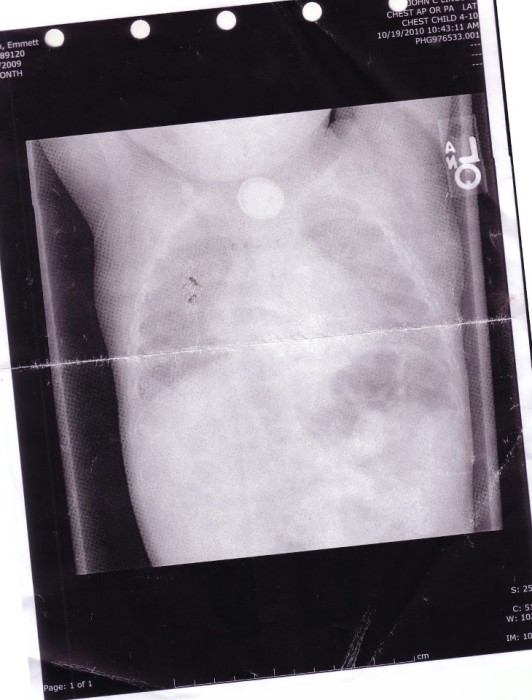

Oui, vous avez bien lu ! Une pile plate venue de la télécommande de la télévision coincée au niveau de son oesophage a été découverte lors des radios. Une fois la pile retirée, le cauchemar a continué. La pile avait distillé son acide dans le corps de cet enfant.